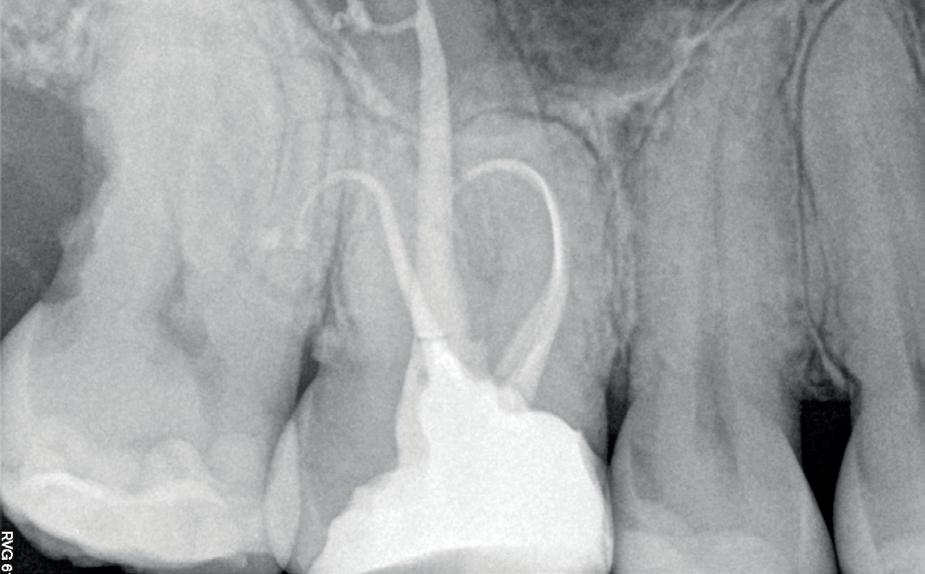

Voordat je aan een wortelkanaalbehandeling begint, zorg je voor (of maak je) een goede beginfoto waar het te behandelen gebitselement volledig op staat afgebeeld. Deze foto geeft essentiële informatie: de grootte van de pulpakamer en de ligging ervan; het aantal en de vorm van de wortels en de breedte van hun wortelkanalen en de lengte van de wortels. Hiermee kan je de DETI-score bepalen en de moeilijkheidsgraad inschatten. De grootte en de ligging van de pulpakamer op de röntgenfoto in combinatie met de ideale anatomische vorm, zoals in foto 1 is aangegeven, bepaalt de uiteindelijke vormgeving van de opening. Bij de molaren liggen de kanaalingangen in de buurt van de knobbeltoppen. Als die niet meer in originele staat

(kroon, restauratie) zijn, kan je ook de wortel gebruiken. Soms moet je net subgingivaal sonderen, maar de kanaalingang ligt in het middel van de wortel. Als je die plek visualiseert en projecteert op je opening, boor je de goede kant op. Nog een tip: wees bij het openen niet spaarzaam met het wegnemen van aanwezig restauratiemateriaal (wees wél spaarzaam met het onnodig wegnemen van tandweefsel).

De casus

De verwijzend tandarts is bezig om een wortelkanaalbehandeling uit te voeren in gebitselement 27. Er zijn vier kanalen gevonden, maar helaas breekt er in het mesiobuccale kanaal (MB 1) een WaveOne vijltje af, maat geel (foto 2). Het lukt de tandarts niet om

1. De locatie van de kanaalingangen ten opzichte van de occlusale morfologie (rood). In zwart is de ideale of standaard opening ingetekend. De uiteindelijke vorm van de opening is voorts ook afhankelijk van de klinische situatie, die vooral vanuit een goede begin foto wordt verkregen.

2. Het afgebroken instrument op de foto van de verwijzend tandarts.

3. De opening is vrij klein gekozen. In rood is de ideale opening aangegeven, de tandarts had veel meer restauratiemateriaal mogen wegnemen.

het vijltje te verwijderen. De patiënte wordt verwezen voor het afmaken van de wortelkanaalbehandeling.

Als ik de patiënte zie, valt me op dat de opening die de tandarts gemaakt heeft, nogal klein is (foto 3). Eigenlijk is daar niet zoveel reden toe; als ik een ideale opening inteken (in rood), dan loopt een groot deel door restauratiemateriaal. Overwogen kan worden om de aanwezige mesiale box met restauratiemateriaal weg te halen als dat het zicht op de pulpakamer vergroot – ik verwijs naar de tip hierboven (wees bij het openen niet spaarzaam met het wegnemen van aanwezig restauratiemateriaal).

Het afgebroken instrument ligt vrij diep; in het onderste 1/3 deel van de wortel. Vaak laten we het afgebroken instrument in het onderste 1/3 deels zitten, omdat verwijderen lastig is en er een kans is op schade. Daarom proberen we het te passeren en wordt het afgebroken instrument onderdeel van de kanaalvulling.

Passeren lukt mij in deze casus helaas niet. Omdat het instrument in een recht deel van het kanaal ligt, waag ik een poging om het afgebroken instrumentje te verwijderen, zodat ik het kanaal kan desinfecteren en kan vullen.

Onder microscopie en met een LN boortje zoek ik het instrumentje op. Na verificatie verwijder ik het door

met een ultrasone tip (Spartan CPR 8, bruin) rondom het vijltje materiaal weg te nemen, waardoor deze als het ware uitgegraven wordt. WaveOne vijltjes zijn irritant om te verwijderen, het nikkeltitanium materiaal wil naar een oorspronkelijke vorm (een rechte vorm) terugbuigen en daarom drukt het zich steeds vast bij het verwijderen. Staal is vaak makkelijker te verwijderen. Maar het lukt me en de wortelkanaalbehandeling kan worden afgemaakt.

Het verwijderen van een afgebroken instrument kost altijd relatief veel (gezond) tandweefsel en kent veel risico op perforatie of andere schade. Daarom is het altijd belangrijk om goed te overwegen of een vijl verwijderd moet worden.

Maar beter nog is om te voorkomen dat een vijltje afbreekt door bij de opening voldoende te prepareren voor goed zicht en voor wat we noemen een ‘straight line access’. Goede voorbereiding is het halve werk.